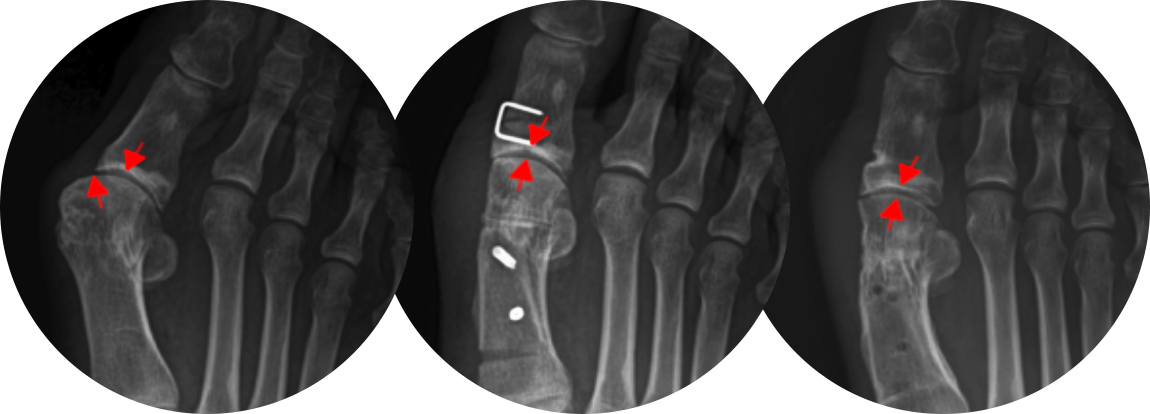

수술 전

수술 후

기구제거 후

* 환자에게 받은 소중한 자료입니다.

첫번째 사진을 보면 중족골두에서 근위지골의 기저부가 완전히 벗어나 있는 것을 확인할 수 있고,

수술 후에는 관절이 잘 맞아 들어간 것을 확인할 수 있습니다.